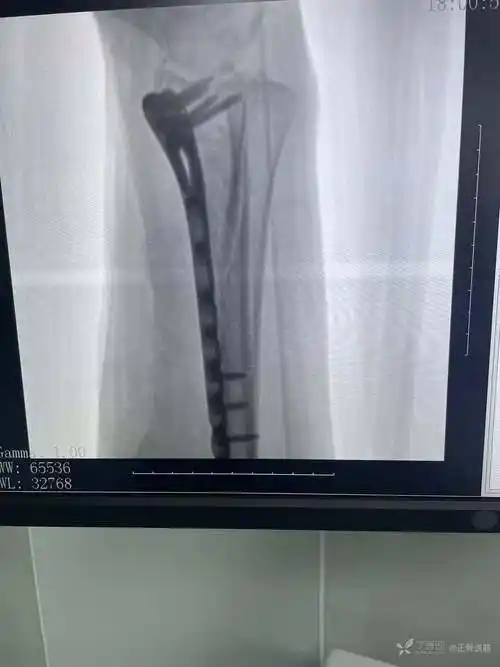

右桡骨远端粉碎性骨折手术一例

拍片示:右桡骨远端粉碎性骨折,关节面不平.